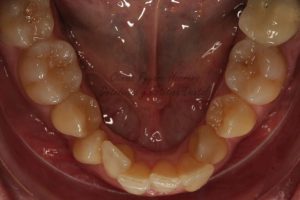

En el momento en el que nosotros le hicimos la exploración clínica vimos que presentaba graves problemas en la salud de su boca. Tal como se puede apreciar en las fotografías que adjunto, el paciente tenía problemas en las encías debido por un lado a la acumulación de placa bacteriana y por otro lado también a que presentaba una maloclusión muy severa. En las fotografías de inicio que le realizamos a este paciente se puede observar cómo presenta mordidas cruzadas en los incisivos y también en los caninos.

Si te fijas en las fotografías que voy a mostrarte las arcadas de la paciente presentaban una forma muy triangular. Los dientes de la paciente no cabían bien a pesar de que ya se había sometido a un tratamiento de ortodoncia con anterioridad en el que se le habían extraído dos premolares superiores y dos premolares inferiores. A pesar de contar con menos piezas dentales, las arcadas eran todavía muy estrechas hecho que provocaba que los dientes no cupiesen y que por consiguiente estuvieran apiñados.